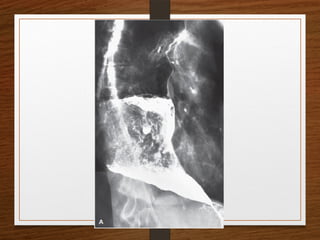

Sigmoid volvulus

The inverted U-shaped loop is usually massively distended

Commonly devoid of haustra, an important diagnostic point.

The ahaustral margin can often be identified overlapping respectively

 the lower border of the liver shadow (the liver overlap sign),

 the haustrated, dilated descending colon (the left flank overlap sign)

 the left side of the pelvis (the pelvic overlap sign).

The top of the sigmoid volvulus usually lies very high in the abdomen

(above the level of T10) with its apex on the left side.

Signs

 Grossly distended loop of sigmoid colon

 Coffee bean sign

 Air – fluid ratio > 2:1

 Lack of haustra

 Apex above 10th

thoracic vertebra

 Liver overlap sign

 Left flank overlap sign

 Pelvis overlap sign

 Bird of prey /twisted bird beak appearance